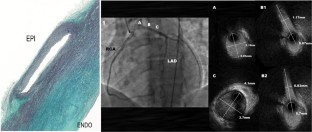

Fig. 1

Fig. 2

Fig. 3

Fig. 4

7. •• Angelini P, Uribe C. Anatomic spectrum of left coronary artery anomalies and associated mechanisms of coronary insufficiency. Catheter Cardiovasc Interv. 2018;92:313–21 Findings from this report explain the wide spectrum of presentation of high-risk cases of left coronary anomalies, based on intravascular ultrasound imaging.

8. • Angelini P, Uribe C, Monge J, et al. Origin of the right coronary artery from the opposite sinus of Valsalva in adults: characterization by intravascular ultrasonography at baseline and after stent angioplasty. Catheter Cardiovasc Interv. 2015;86:199–208 This report explains the fundamental mechanism of ischemia in any coronary anomaly with an intramural course, as shown by intravascular ultrasound.